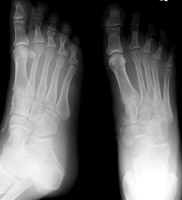

Cuneiform fractrures generally occur in conjunction with other fractures of the midfoot. In particular, the LisFranc dislocation is often associated with cuneiform fractures.

- Click on the image for a larger versionAAP and oblique radiographs of the foot. A car ran over the foor of this patient. There is a comminuted fracture of the medial cuneiform bone along with fractures of the navicular and first metatarsal.